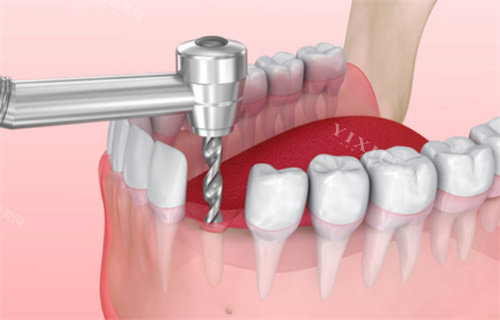

种植牙项目:

普通医生种植手术费:2000元/颗

院长级种植手术费:5000元/颗